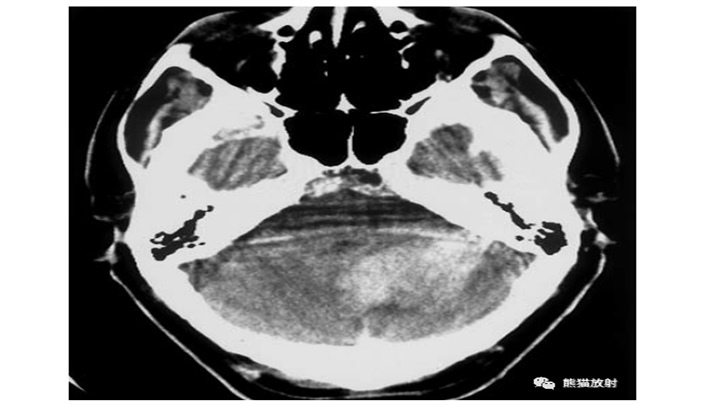

8岁女孩突然昏迷。小脑IPH伴蛛网膜下腔出血,脑干缺血性密度减低,脑积水(侧脑室颞角扩大)。小脑蚓部是“隐性血管瘤”最常见的部位之一。